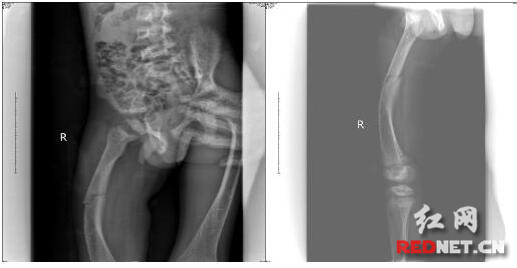

复位后小博强X光片

9岁的小博强不慎于10月16日在学校一下坡处滑倒,右大腿无法动弹并伴有持续性疼痛,让他止不住哇哇大哭,老师紧急将其送往娄底市骨伤医院。入院后,完善相关检查,诊断为“右股骨骨折”,遂收住髋股膝胫科。“怎么的了啊,我的崽啊,怎么摔的那么严重啦…”患儿的妈妈哭着赶到医院。据悉,患儿家境贫苦,因其母腿部患有先天畸形,家中四姊妹有三个大腿是先天畸形。了解到小博强家庭困难,医院决定为其开辟绿色通道,因有先天畸形,院领导召集专家会诊并制定合理的治疗方案,旨在竭力为其提供高超的技术和优质的服务。在欠费的情况下,医院采取了传统中医手法复位+小夹板固定治疗,手法复位后骨折端对位对线解剖复位,免除了手术治疗带来的痛苦,避免了手术治疗的高费用及愈后再次手术带来的损伤。考虑到患儿年龄小、好动,且患儿骨折断端在股骨畸形的应力处,随时有移位的可能,科室采用皮牵引配合小夹板治疗。为促进患儿骨痂生长,医院坚持给予中药和物理治疗。闲暇之余,髋股膝胫科的护士姐妹们不忘到病房和小博强聊聊天,将自己好吃的东西分享给他,让小博强在医院的每一天都忘记病痛过的开心。

11月17日,经复查X光片,小博强骨折端已有丰富的骨痂生长,患肢功能良好,骨折愈合坚固。为防止小博强在家将小夹板移位造成再次损害,医院给予石膏外固定。出院时,小博强的妈妈激动地说“骨伤医院真是我崽的再生父母,在我们欠那么多钱的情况下,坚持给予治疗,果真是医者仁心,往后我将教导博强努力学习,回报社会”。

据卞志超医生介绍,儿童处于生长发育期,骨质柔嫩、骨膜厚韧,无论从高处跌下还是重物压砸,都易发生骨折。因儿童成骨能力强、骨折愈合快、具有较强的塑形能力,可以采用创伤小的传统手法复位。但手法复位,需以合理的固定为治疗的中心环节。皮牵引结合小夹板固定,在儿童股骨骨折的治疗中具有愈合优良、住院时间短、疼痛消失快、固定牢靠、制作简便、便于护理观察等优势。(编辑/李梅花)